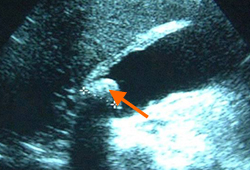

- ultrassonografia abdominal